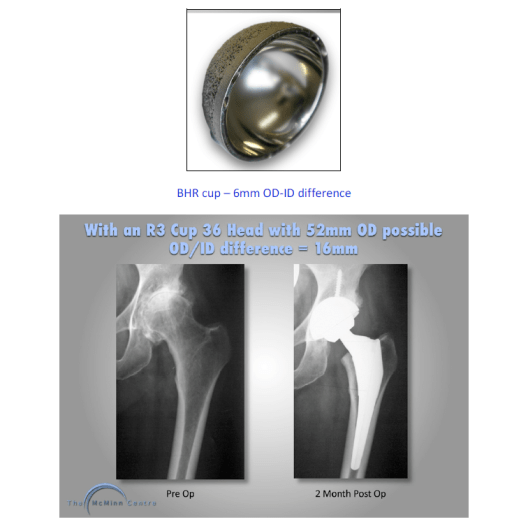

This effectively means that the wall thickness of the acetabular component has to be 3mm. 3mm happens to be the thickness of the acetabular wall of the BHR and this gives an out-diameter to inner-diameter (OD-ID) difference of 6mm.

It can clearly be seen that the minimum OD-ID difference of 16mm with a total hip replacement using a titanium acetabular shell and a cross-linked polyethylene liner is quite different to the to the 6mm OD-ID difference using the BHR.